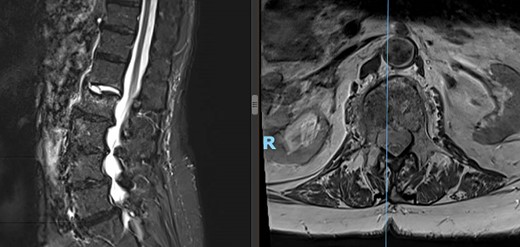

The patient is an 82-year-old female with a history of hypertension and osteoporosis with BMI of 34.39. The patient presented with worsening, 10/10 lower back pain for the past 3 weeks, which interfered with her ability to perform activities of daily living (ADLs). Her pain started in the midline lumbar spine, radiating laterally across her back into her buttocks and bilateral groin. MRI with no contrast of the lumbar spine revealed L2 compression fracture with concurrent injury to the L1-L2 disk (Fig. 1). The patient was referred to interventional radiology (IR) for L2 kyphoplasty.

Preoperative lateral (left) and axial (right) MRI of the patient’s spine showing L2 compression fracture.